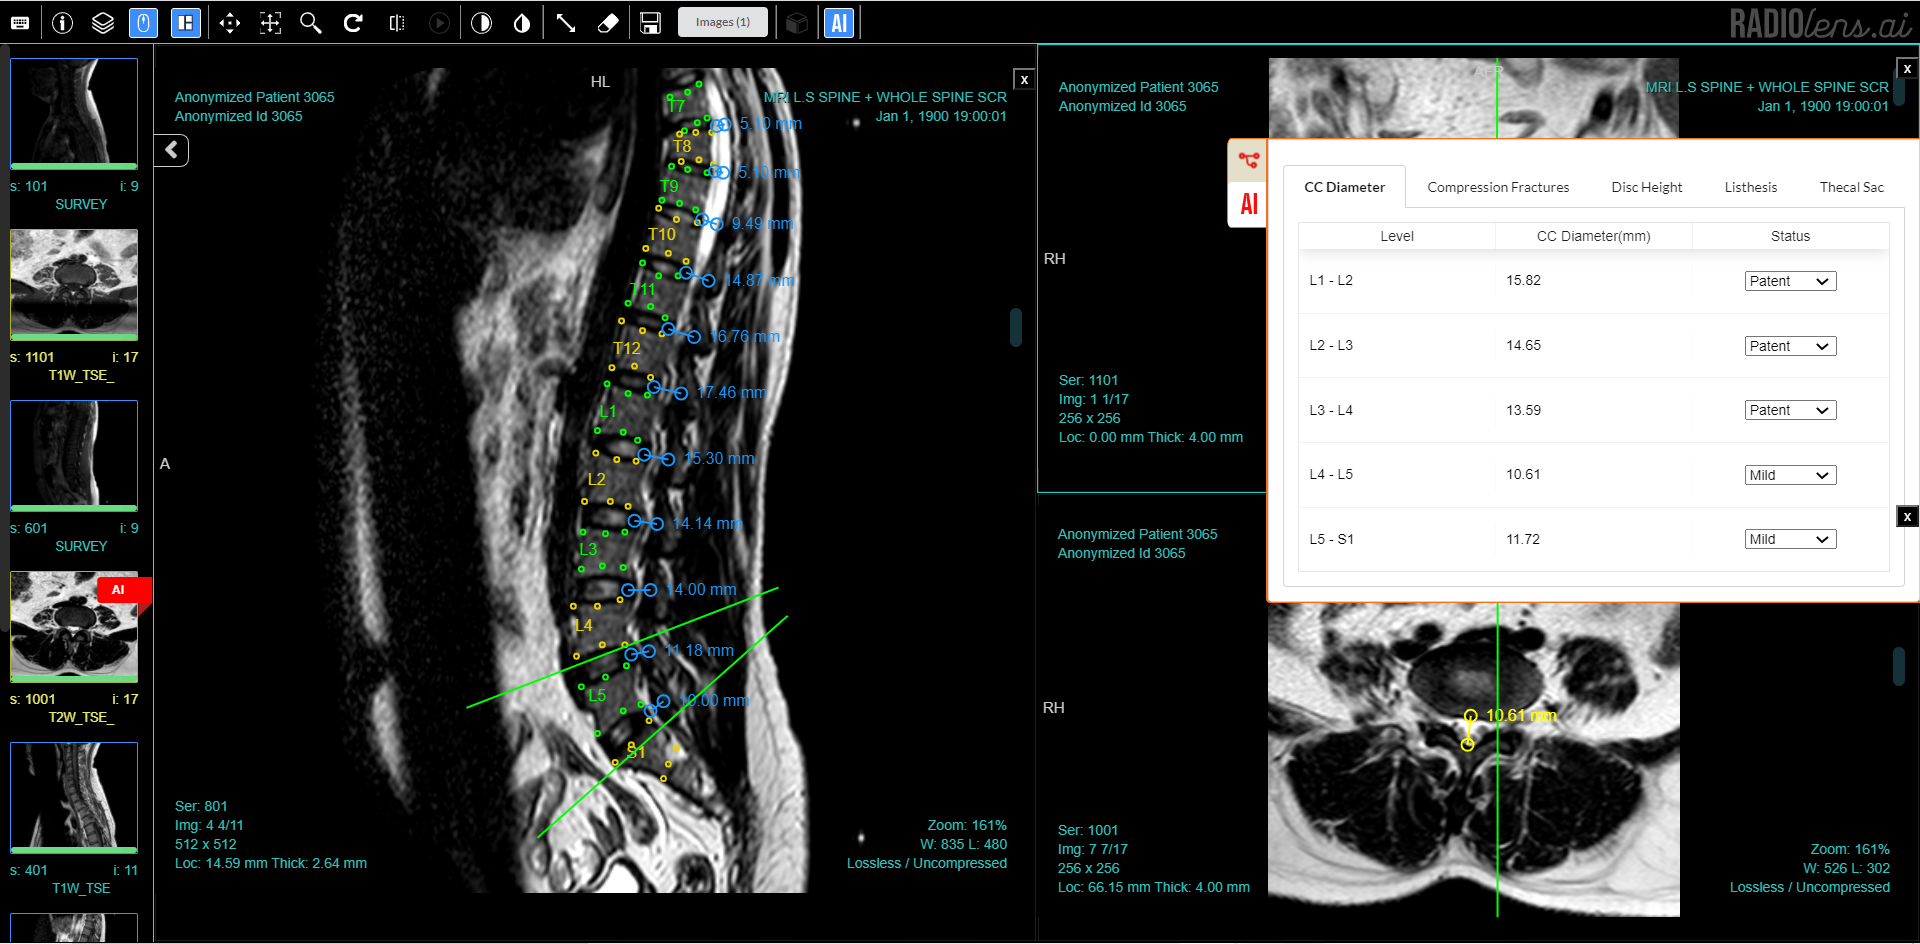

With three intelligent algorithms / AI reporting assistants working in sync with our PACS/ RIS solution RADIOLens we have seen major improvements in turn around time and accuracy rates for reporting and increased trust among all parties involved.

- Synapsica Spindle: An AI reporting assistant for MRI Spine that generates preliminary reports with necessary spinal measurements and characterisation of degenerative diseases.